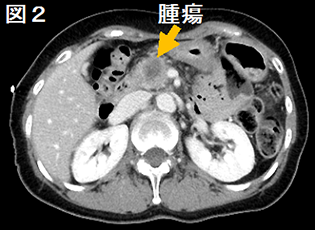

b) CT, MRI検査

膵がんは浸潤する力が強いため、周囲の膵組織との境目がはっきりしないことが多く、CTやMRI(核磁気共鳴検査: 磁石の力で体の中を検査する方法)では判定しにくいことが多いです。膵管が詰まった場合は、流れの悪くなった膵液で膵管が拡がってきますので、それを目安に腫瘍の位置がわかることがあります。MRIでは液体を強調した画像を作ることが出来るため、膵液や胆汁を強調して膵管や胆管への影響を把握することも可能です。最近ではMRIの拡散強調画像という撮影方法によって、腫瘍の硬さから悪性度を判断する方法も行われております。また、肺や肝臓など他の臓器に膵がんが転移していないかも調べることができます。

図3 MRI拡散強調画像

MRI拡散強調画像